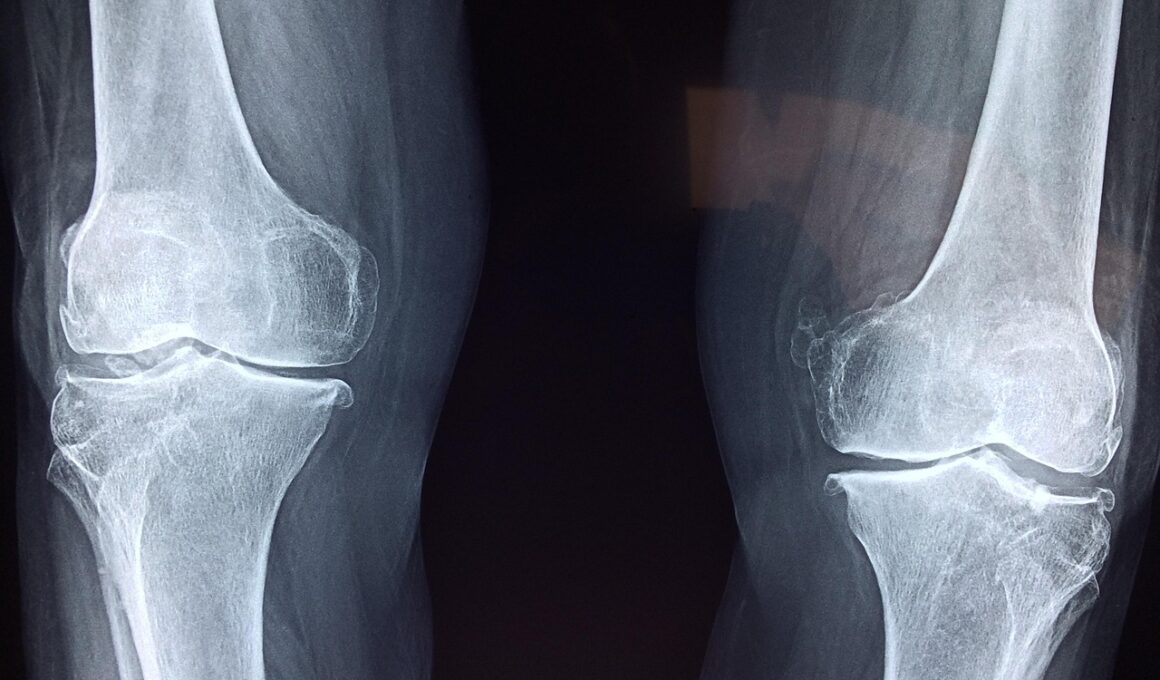

Another key focus of celiac disease awareness should be bone density screening, especially for patients who have been diagnosed later in life. The relationship between celiac disease and bone health indicates that individuals may not exhibit symptoms until significant damage has occurred. Therefore, obtaining a dual energy X-ray absorptiometry (DEXA) scan can provide valuable insight into a patient’s bone density status. DEXA scans help detect early signs of osteoporosis, allowing for timely intervention that can help protect bone health. Healthcare providers should encourage patients to consider periodic screenings, particularly for those with a history of fractures or arthritis. Additionally, understanding the importance of maintaining bone health through diet and lifestyle is essential for individuals with celiac disease and those affected by gluten intolerance. A well-balanced, gluten-free diet rich in calcium and vitamin D should be prioritized. Furthermore, participating in weight-bearing exercises has been shown to strengthen bones and improve overall health in patients. By focusing on prevention and awareness of the risks, individuals can significantly mitigate potential consequences on their bone health associated with celiac disease.